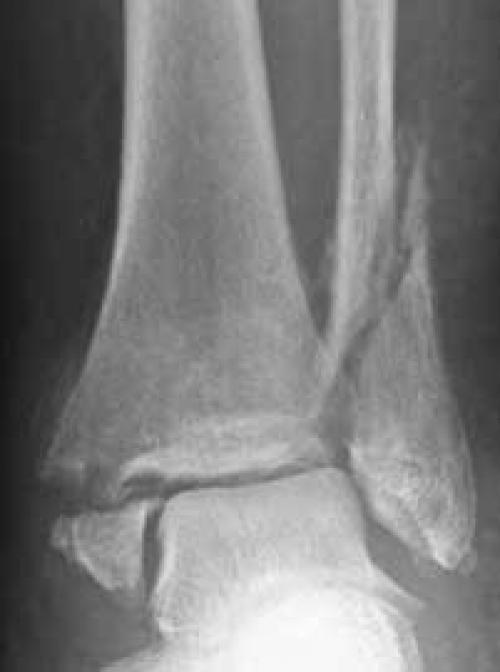

Обычно, отламываются лодыжки: внешняя (латеральная, – отросток малоберцовой кости) или внутренняя (медиальная – часть большеберцовой). Могут ломаться и сразу обе.

Рис. 2. а. перелом обеих лодыжек со смещением; б. перелом лодыжек и заднего края большеберцовой кости.

Особенность таких переломов в том, что иногда щиколотки как бы отрываются от костей голени: при подворачивании ноги, прочные связки могут не разорваться, а тянут за собой щиколотку, отрывая или ее полностью, или вызывая отлом и смещение небольшого фрагмента кости.